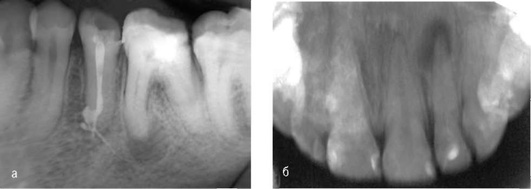

Форма и размер гиперцементоза могут быть различными как на рентгенограмме (рис. 13-2), так и на удалённых зубах (рис. 13-3, см. цв. вклейку).

Следствием воспалительного процесса может быть резорбция альвеолы костной ткани и цемента корня (рис. 13-4).

image

Рис. 13-2. Гиперцементоз: а - гистологический срез; б - рентгенограмма зуба 45

Рис. 13-4. Резорбция альвеолы костной ткани и цемента корня зубов: а - зуба 22; б - зубов 31 и 41